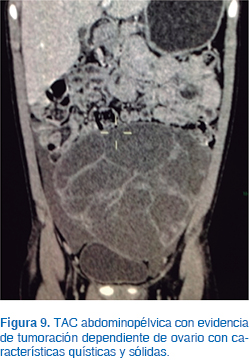

Se inició protocolo de estudio. El USG mostró tumor con ecogenicidad mixta (Figura 8); la TAC abdominopélvica evidenció una masa dependiente de ovario con características mixtas, quísticas y sólidas de 15 x 20 cm de diámetro (Figura 9). Los estudios de laboratorio indicaron alfa fetoproteína de 1.6 μg/L, fracción β de la gonadotrofina coriónica de 1.4 mUI/mL; LH, 6.2 mUI/mL; FSH, 7.4 mUI/mL; prolactina, 16.3 ng/mL; estradiol, 2.1 pg/mL, y 17-OH PROG, 0.6 ng/dL.